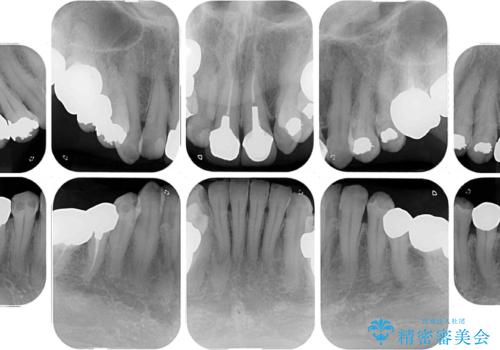

奥歯の銀歯は、セラミッククラウンを装着するには歯の高さが不十分であり、そのままでは矯正治療を行うことが困難であるため、歯冠長延長術を行うこととしました。

また、根管治療の必要な歯がいくつかあるため、歯周外科治療の治癒期間を利用して根管治療を行い、その後インビザラインにて矯正治療を行うこととしました。

矯正治療後にはオールセラミッククラウンにて補綴治療を行うこととしました。